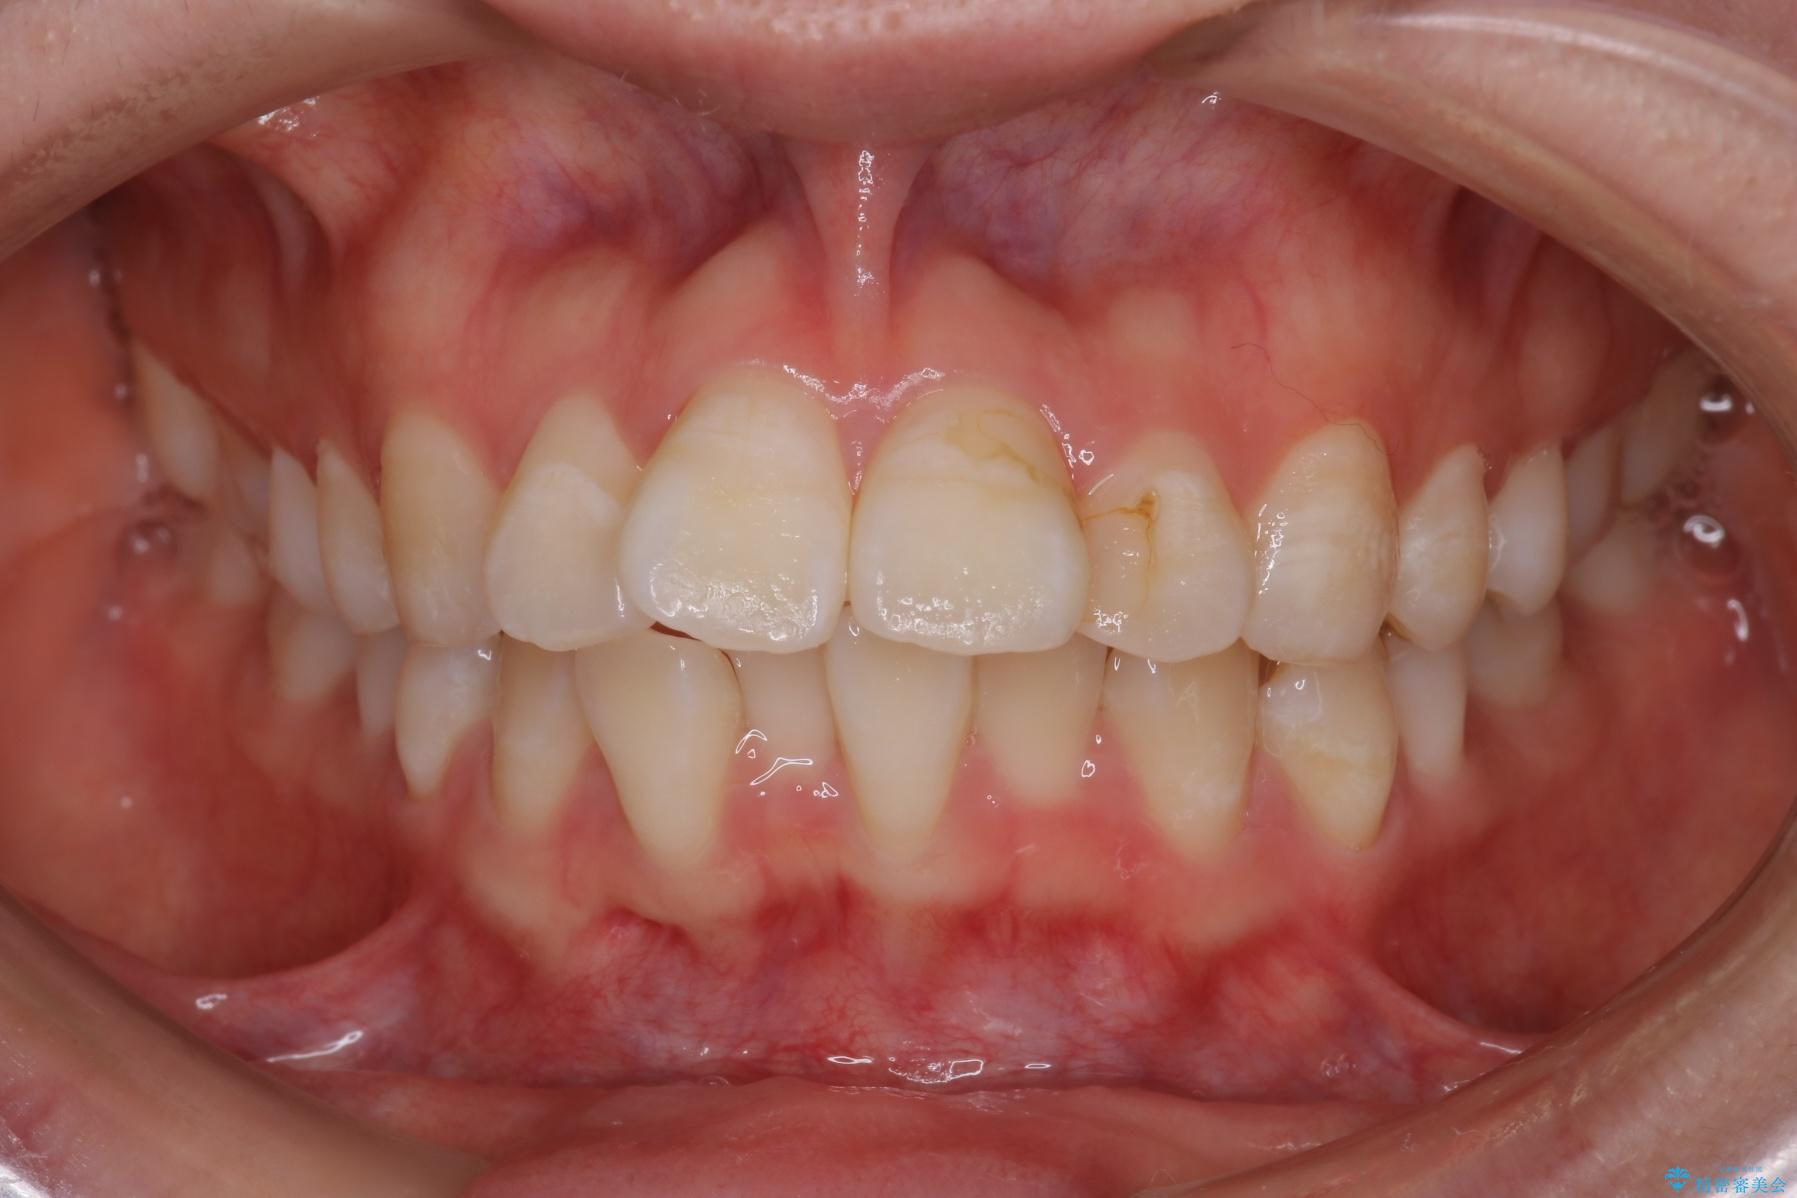

前歯のガつきと口元が出ていることを気にされご来院された患者様です。

上下4番目の歯を抜歯してガタつきを改善しながら口元を下げる治療計画を立てました。

抜歯矯正で口元を下げたことで、Eラインが大変綺麗になりました。